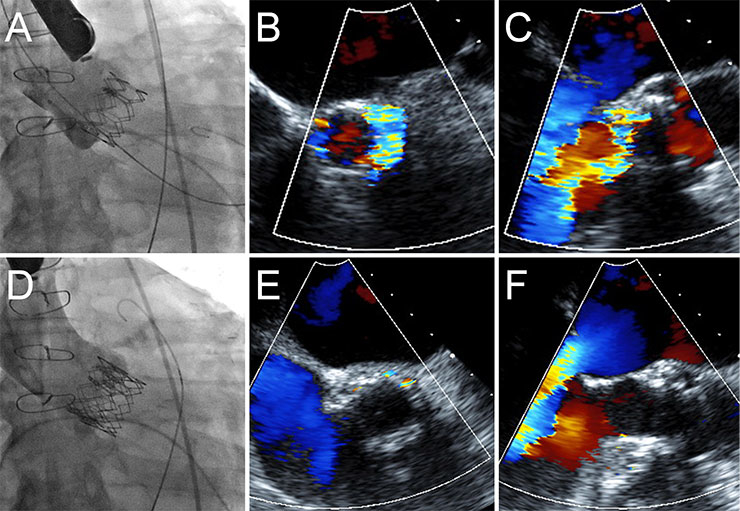

Figure 2

Treatment of paravalvular regurgitation by implantation of a second transcatheter heart valve. In patient, the TEE measured an annulus of 22 mm. A 26 mm Edwards Sapien XT valve was implanted (A). A low implantation resulted in severe paravalvular aortic regurgitation (B, C). A second 26 mm valve was subsequently implanted in a higher position, thus extending the annular seal (D) resulting in a mild paravalvular leak (E, F).

If relevant PAR occurs, the next step is to assess whether or not the valve is deployed in the correct position. If the valve is in the correct position postdilation may reduce the degree of PAR. If the valve appears undersized after postdilation the options are more limited, although paravalvular leak closure may be considered an option. However, most of the published data relate to paravalvular leak closure with surgically implanted valves, and experience with transcatheter valves is limited [29]. With transcatheter heart valves the shape of the leak may be circumferential and more than one leak may be present, making paravalvular leak closure more difficult or even impossible. In the event of malpositioning of the first valve, a second valve can be implanted higher (if the initial implant is too low) or lower (the initial implant is too high) than the first valve (fig. 2 ). The goal is to extend the sealing fabric in such a way that the sealing fabric of both valves overlaps and that the second valve ensures sealing with the native valve annulus [30, 31]. The same valve size is used for both valves.